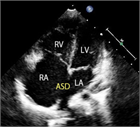

1. 心室中隔欠損は、欠損孔の部位により、膜性周囲部(perimembranous)、筋性部(muscular)、漏斗部または肺動脈弁下部(subarterial)に分類され、自然歴、手術適応が各々異なるため、部位診断は重要である。